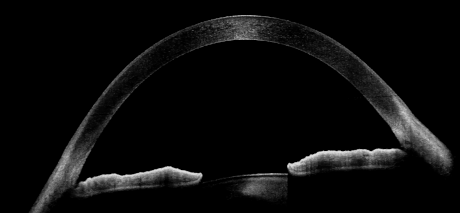

Full Range-Aufnahmen

Das Extended Depth Retina Imaging, welches auf der Full Range-Technologie basiert, bietet Scans mit größerer Tiefe für eine zuverlässige und bequeme Kontrolle von schwierigen Fällen. Dank der Scans mit großer Tiefe ist dieser neue Bildgebungsmodus perfekt für die Diagnose von sehr stark kurzsichtigen Patienten geeignet. Außerdem bietet sie einen Überblick über die gesamte Vorderkammer, von Hornhaut bis zur Augenlinse.

- Darstellung des vollständigen vorderen Systems

- Messung beider Kammerwinkel in einer Aufnahme

- Automatische Pachymetrie

- Analyse des Kammerwinkels

- Darstellung der Iris

Zusätzlich existiert ein Scan-Programm zur detaillierten Darstellung der Vorderkammer.